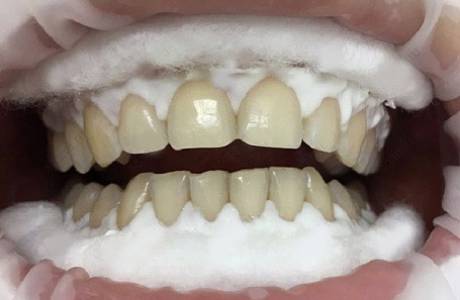

До лечения

Пациент обратился с жалобой на разрушение зубов.

После лечения

На верхней челюсти было принято решение установить E-max коронки.На нижней челюсти E-max виниры. Пациент полностью доволен свой новой красивой улыбкой.